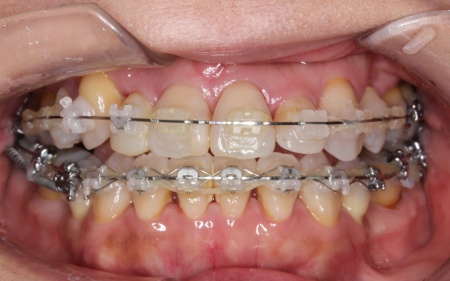

治療後

最後に、歯並びや噛み合わせがしっかりと改善されたことを確認し、治療を終了しました。

治療期間 3年

費用 約1,019,500円

【CTレントゲン、術前診査検査、

ハイブリッド矯正(透明なブラケットと金属製のブラケットを併用したワイヤー矯正)、抜歯(4本)、インプラントアンカー、調整料24回分】